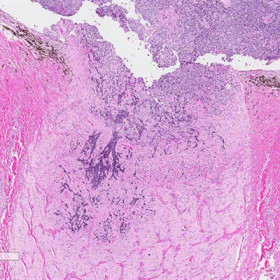

Retinoblastoma

Both gross and histopathologic images of retinoblastoma invading the optic nerve. Images courtesy of Tatyana Milman, MD